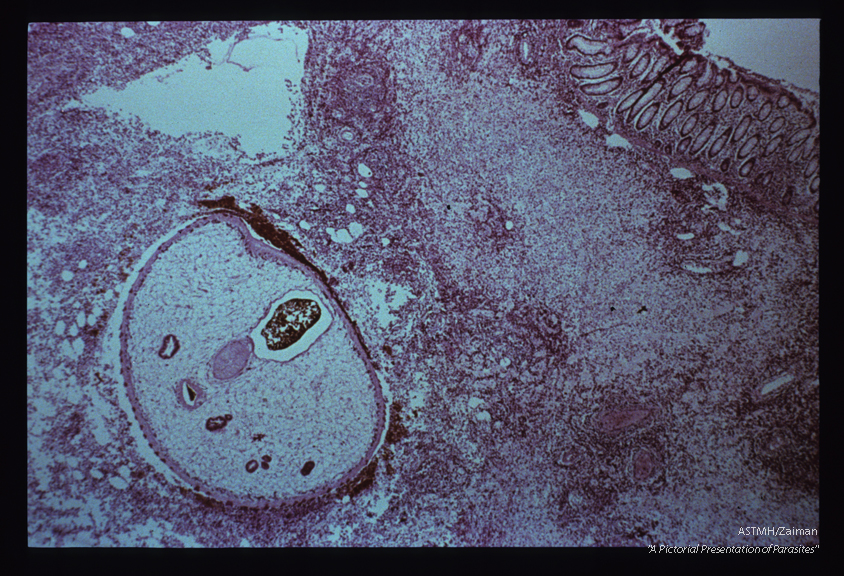

Adult embedded in intestinal wall. The parasite presents as an oval to round mass limited by a spined cuticle. The parasitic parenchyme is punctuated by multiple sections through gut (reddish-brown). The two centrally located tubular structures, separated by a light staining muscular sucker, are part of the reproductive apparatus of the parasite. A marked inflammatory response is present in the adjacent host tissues and fresh red blood cells can be seen near the parasite.

Fasciola hepatica